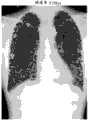

Figure 10 is analysis result and the figure of the evaluation result in processing time of the representative items of the dissection process of expression when making the piece change in size of zonule.

Figure 11 A is that expression makes piece be of a size of the figure of the analysis result of the Peak Flow Rate ratio of 2mm when square.

Figure 11 B is that expression makes piece be of a size of the figure of the analysis result of the Peak Flow Rate ratio of 5mm when square.

Figure 11 C is that expression makes piece be of a size of the figure of the analysis result of the Peak Flow Rate ratio of 10mm when square.

In the rectangular histogram of Peak Flow Rate ratio is resolved; Such shown in Figure 11 A~Figure 11 C etc.; The value of the ratio of the maximum (absolute value) of the inspiratory airflow speed of each zonule and the maximum (absolute value) of expiratory airflow speed represented by rectangular histogram, and generates to show whether become be the whole meansigma methods of the lung field of index of COPD, the image of standard deviation.And, through the such diagnostic message of representing each zonule on the still image with brightness corresponding or color simultaneously, can provide to make the doctor can confirm unusual position easily of distribution with ratio.